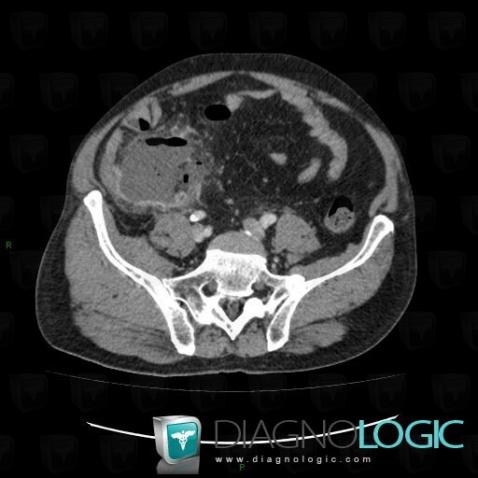

Appendicitis, Caecum / Appendix, CT

Here is the specific information in the key image above:

- Diagnosis Appendicitis, Location(s) Caecum / Appendix, with gamuts